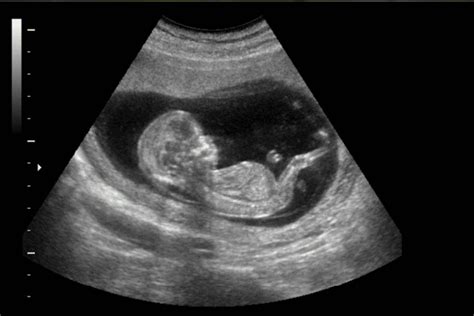

La ecografía fetal es una herramienta fundamental tanto para la emoción de los futuros padres como para el control médico del embarazo. Permite visualizar el desarrollo del bebé, evaluar su crecimiento, la cantidad de líquido amniótico y la posición de la placenta. En algunos casos, la ecografía ayuda a detectar posibles complicaciones o diagnosticar problemas médicos.

Durante el procedimiento, se utiliza un transductor que emite ondas sonoras. Estas ondas, al rebotar en el feto y los tejidos circundantes, se transforman en una imagen en una pantalla. Los riesgos asociados a la ecografía fetal son bajos, pero se recomienda su realización únicamente por motivos médicos y bajo supervisión profesional.

En las primeras etapas del embarazo, alrededor de las 11 semanas de gestación (nueve semanas después de la concepción), la cabeza del feto ocupa aproximadamente la mitad de su longitud total.